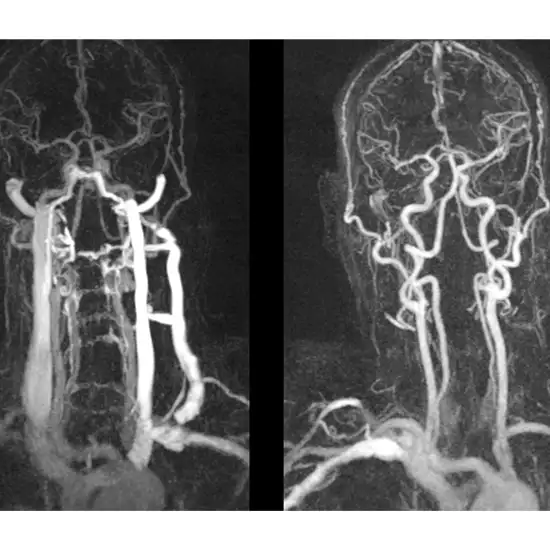

A CT Neck Angiography is an imaging procedure to obtain detailed images of the arteries of the neck and the blood vessels present in both the neck and head region. For this scan, an x-ray beam and contrast media are used to visualize the blood flow. It is also known as a carotid angiogram. Doctors order this scan for patients with symptoms such as weakness and numbness in the face, numbness in one side of the body, trouble in speech, dizziness, loss of balance, severe headache, etc. This scan is useful in identifying weakened arteries and veins. It helps in monitoring the blockages or narrowing of arteries.